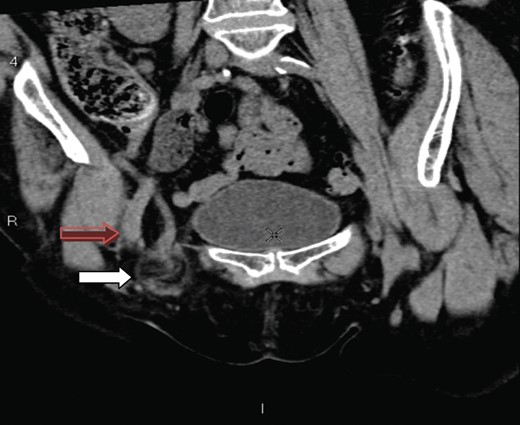

A 70-year-old female was referred by her general practitioner to our radiology department after presenting with a painless right groin swelling. An ultrasound scan showed a lymph node in the right groin with surrounding fluid and unusual appearances not typical of a hernia. A limited CT scan was subsequently performed which revealed a right femoral hernia containing the tip of the vermiform appendix with surrounding inflammatory change and an associated enlarged lymph node in keeping with a De Garengeot's hernia (Figs 1–3). On questioning, the patient first noticed the lump 2 weeks prior to presentation and said that it has gradually increased in size. It was not painful and she had no obstructive symptoms. Her medical history included COPD, breast cancer and a past history of tuberculosis.

A axial section illustrating a right femoral hernia through the femoral canal at the level of pubic tubercle.